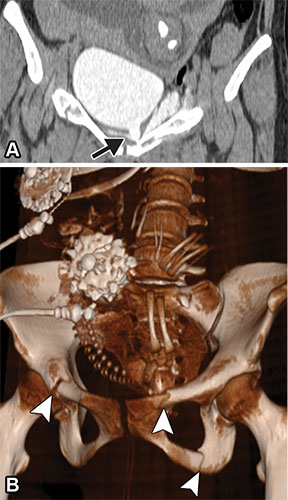

Extraperitoneal bladder rupture in a 24-year-old woman at 29 weeks of gestation after experiencing trauma. Coronal CT cystogram (A) and three-dimensional (3D) reconstruction CT image (B) show extraperitoneal extravasation of contrast material–opacified urine (arrow in A). Multiple pelvic fractures are seen on the 3D reconstruction image (arrowheads in B), in addition to the fetal skeleton. In a patient with a pelvic fracture, evaluation with cystography or delayed imaging is reasonable despite the additional radiation exposure. Attention should be given to potential fetal skull fractures (see Fig 8).